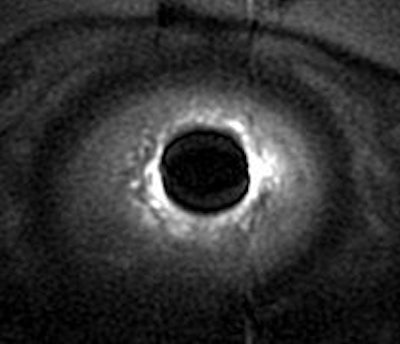

| Strain imaging steady-state fast spin echo (SSFSE) of urethra mobility and bladder neck competence assessment. Note hypermobility of urethra that assumed horizontal position and bladder neck funneling (arrow). Image courtesy of Dr. Katarzyna J. Macura, Ph.D., Johns Hopkins University. |